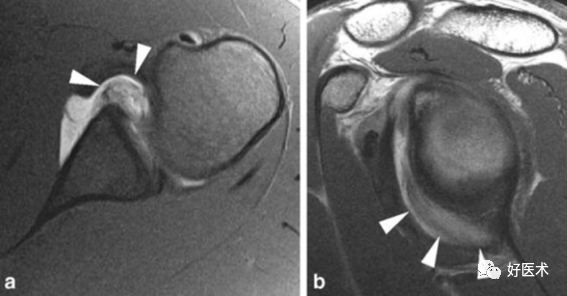

1.Bankart lesion

盂肱下韧带和前盂唇(前下盂唇韧带复合体)从关节盂边缘撕脱,伴肩胛骨骨膜的撕裂。首次损伤后不恰当愈合可导致反复肩关节不稳。

2.Bony Bankart lesion

前下盂唇韧带复合体从关节盂边缘撕脱,伴继发于前关节脱位的肩胛盂骨性骨折。

3.Perthes lesion

Bankart lesion的变异:前下盂唇韧带复合体从关节盂边缘脱离,但骨膜完整且向前内侧剥脱,因此盂唇可在正常解剖位置。